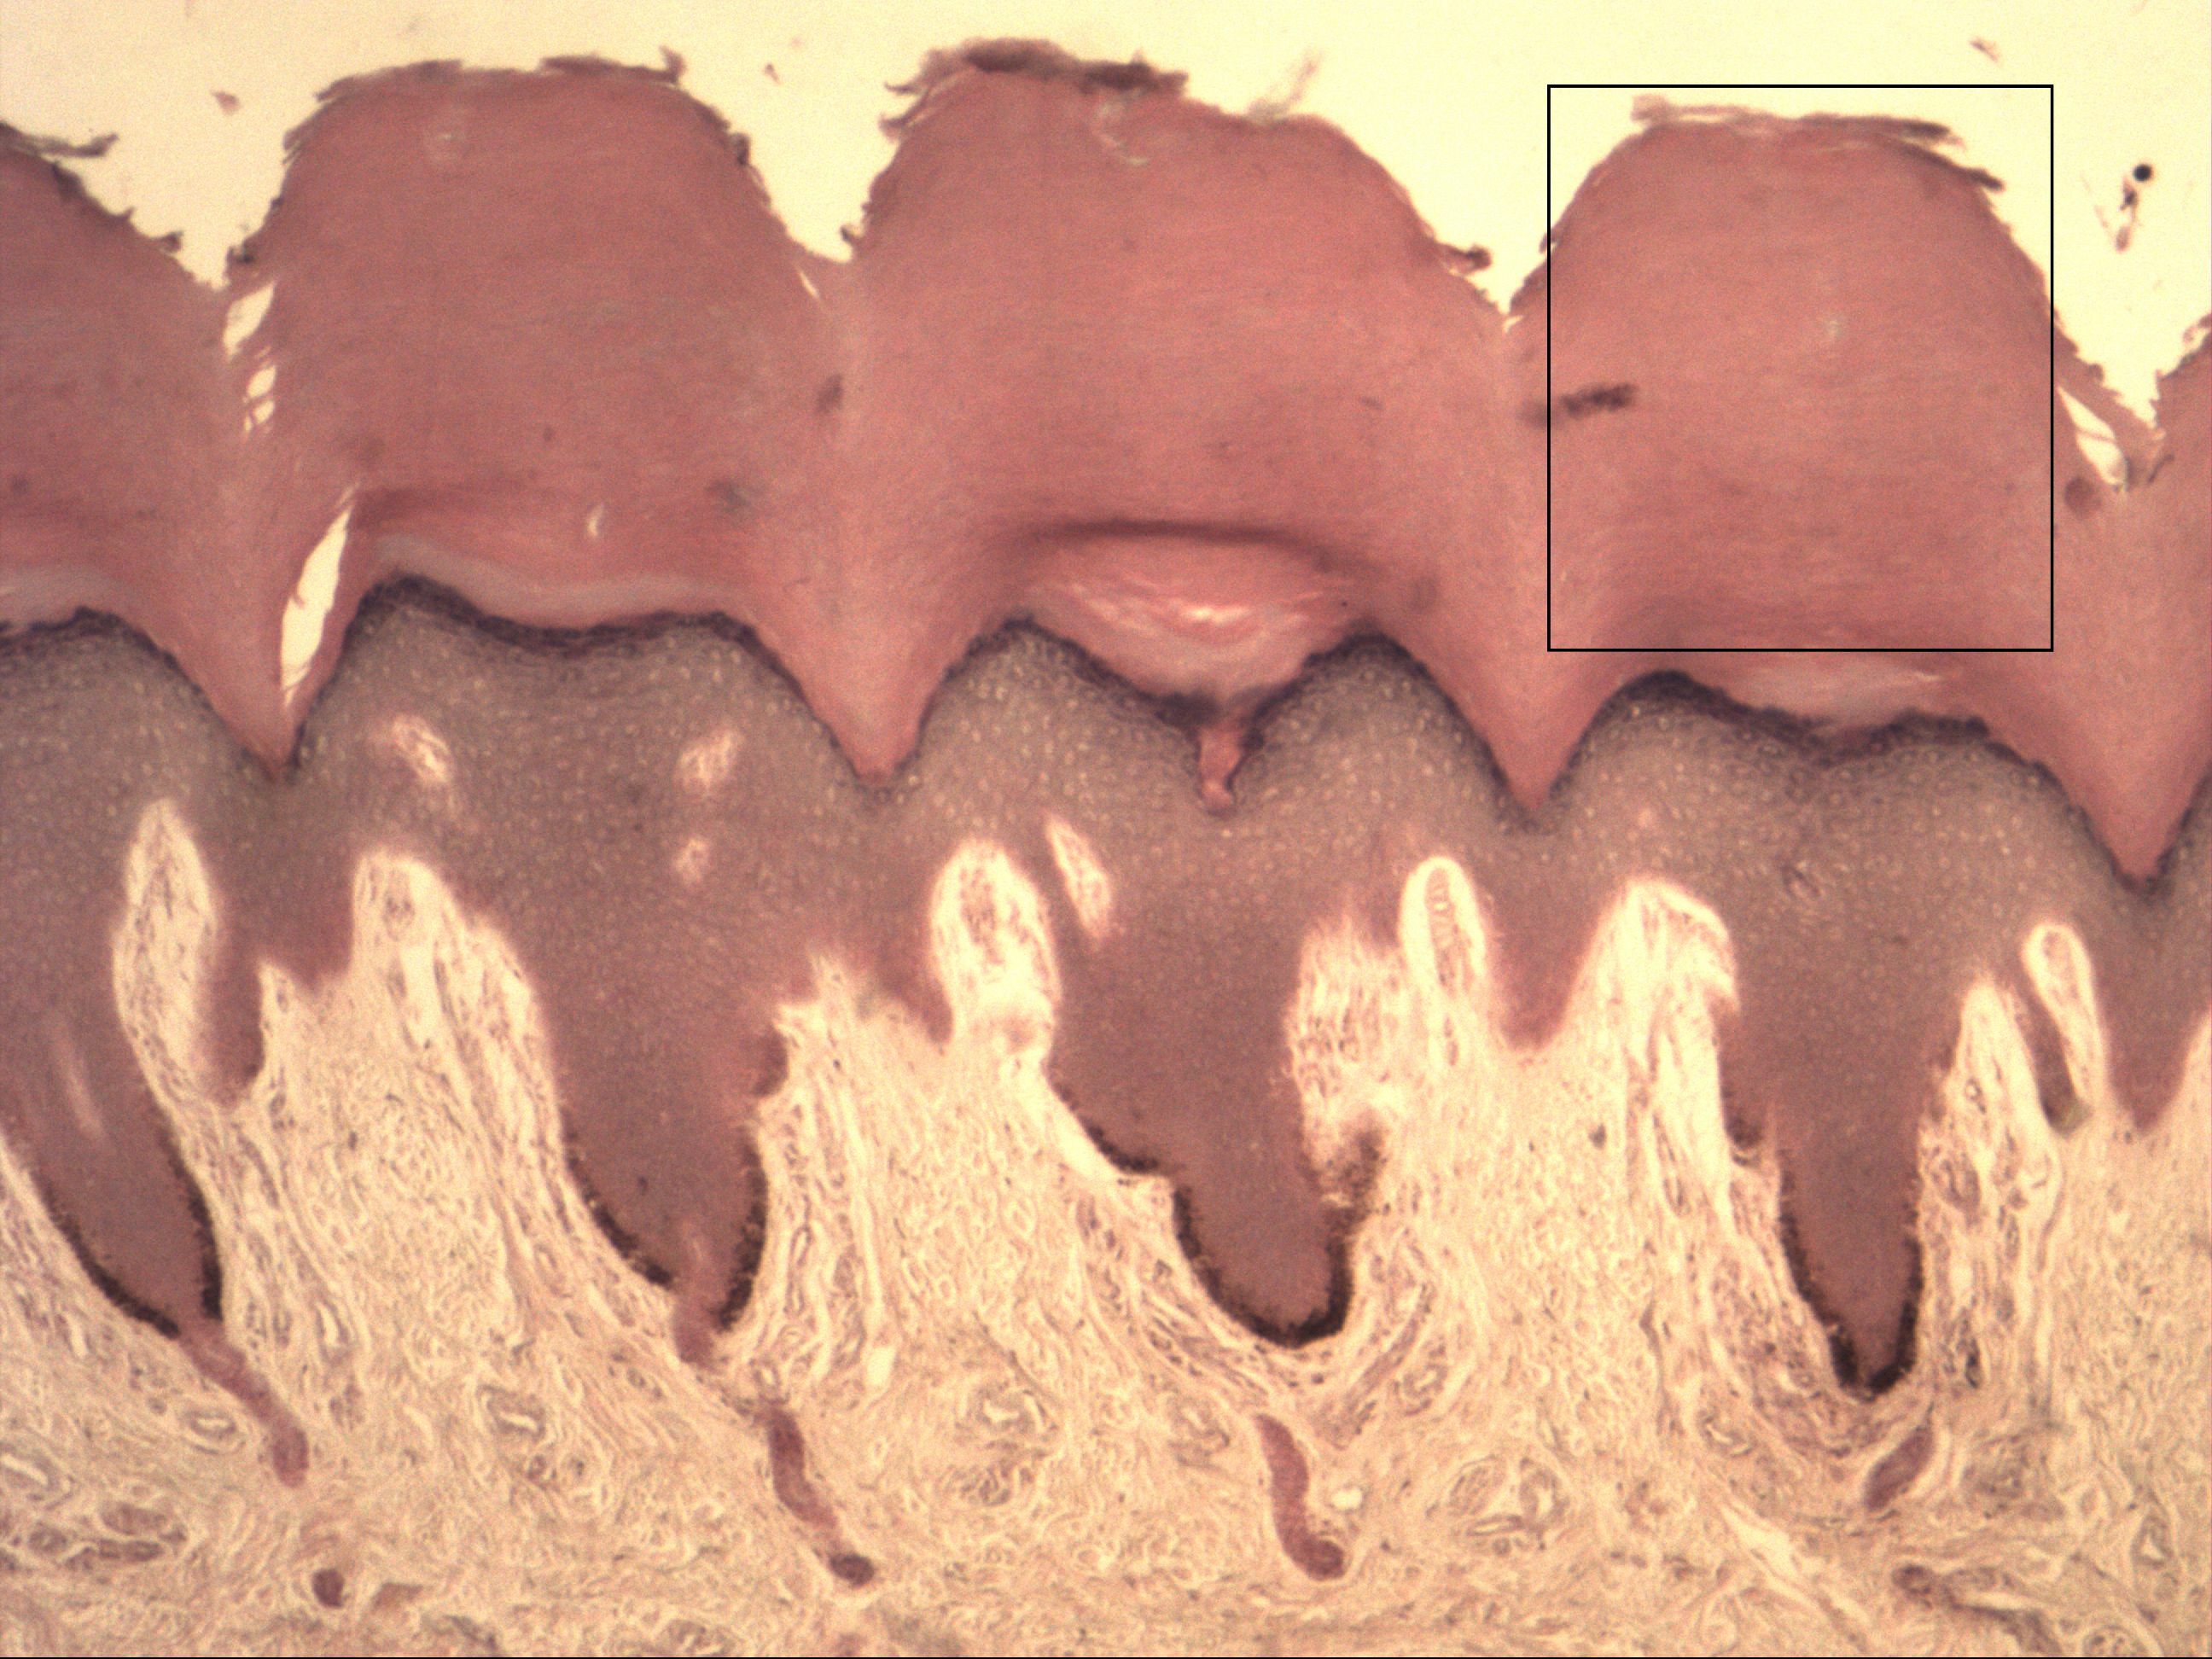

Mehrschichtig verhorntes Plattenepithel

Fingerbeere [HE]

Das mehrschichtig verhornte Plattenepithel findet man beim Menschen ausschließlich in der Epidermis. Die Haut wird als Cutis bezeichnet, das unterliegende Gewebe als Subcutis (Fett und lockeres Bindegewebe, Mechanorezeptoren, Nerven). Die Cutis gliedert sich in die Epidermis und Dermis/Corium. Das Epithel (Epidermis) besteht aus den Schichten Stratum corneum, Stratum lucidum, Stratum granulosum, Stratum spinosum, Stratum basale. In die Basalmembran einstrahlende Bindegewebsfasern werden durch Ankerfibrillen befestigt. Die Dermis beherbergt das Stratum papillare und auch die Talk- und Duftdrüsen.